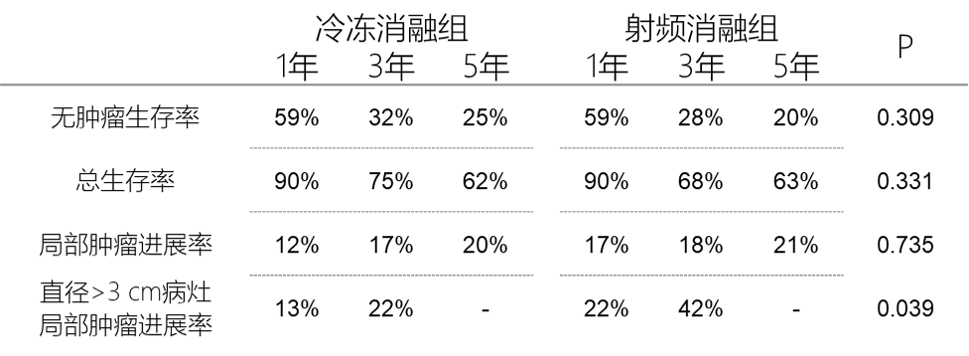

② 无肿瘤生存曲线和总生存曲线

③ 局部肿瘤进展率曲线和直径>3 cm病灶局部肿瘤进展率曲线